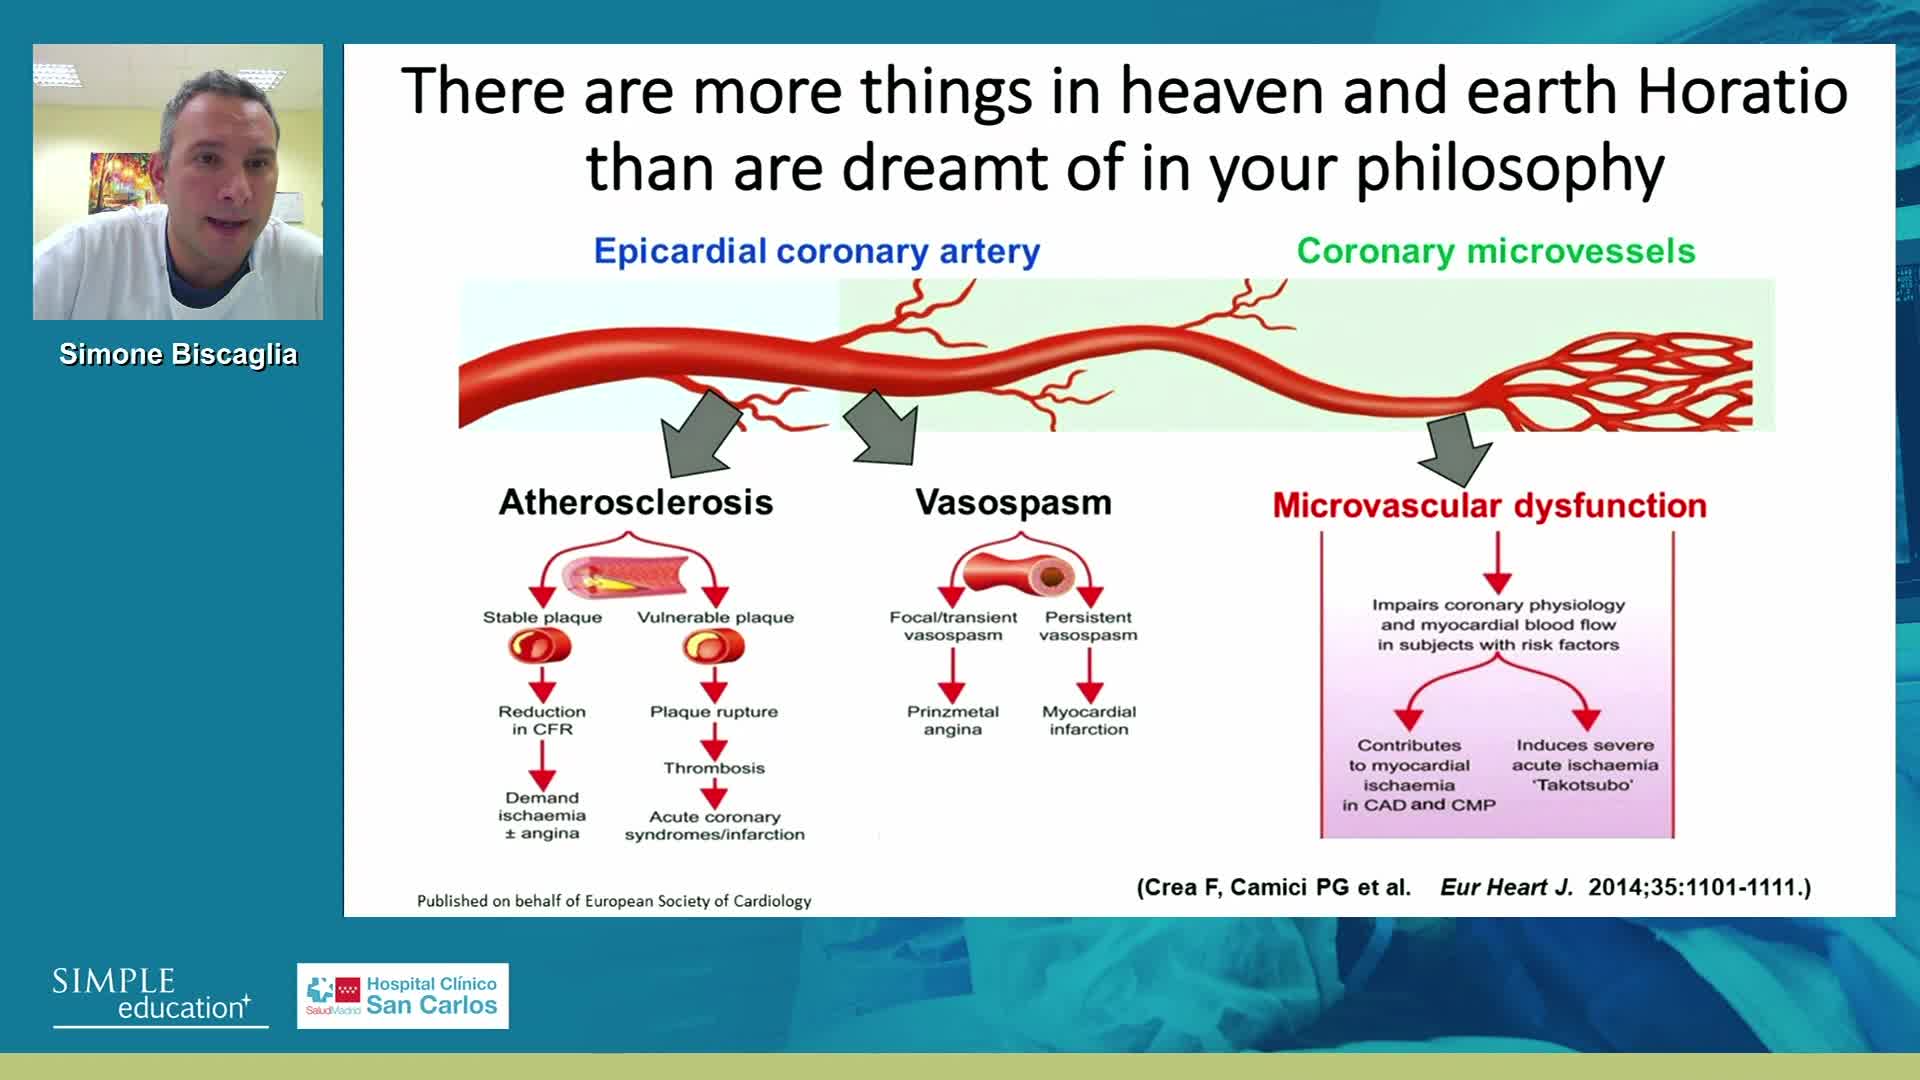

Why is the physiology negative? Integration of the coronary microcirculation to decision-making